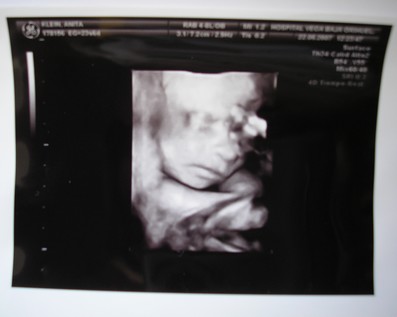

A kisbabád meg nagyon szép, nagyon jó kép lett róla. Olyan jó, hogy kislány lesz, nagyon sok szép kisasszonynév van, bő a választék. Bezzeg fiúból... ezért nincs is még lekonkretizálva mindig a mienké, de nem lesz nevesincs királyfi, az tuti